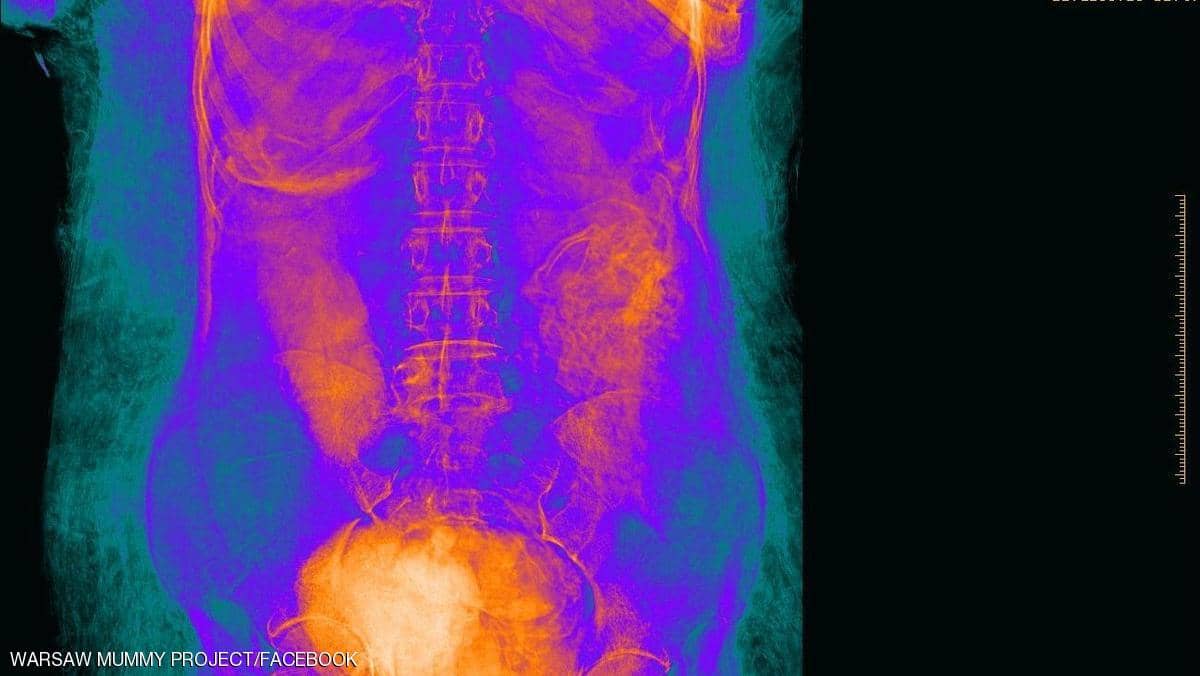

كشف مجموعة من علماء علم الآثار مومياء مصرية ضمن المومياوات الموجودة في متاحف العاصمة البولندية، وفي بداية الكشف ظن العلماء أن المومياء لكاهن يدعى "حو جحوتي"، وعندما زاد شك العلماء في حجم المومياء تم الاتفاق لعمل أشعة مقطعية لها، وبالفعل وضعت المومياء المصرية أمس تحت جهاز الأشعة، وبعد وضعها تحت الجهاز صار العلماء مندهشين بسبب ما أخرجته الأشعة والتي أوضحت أن المومياء لمرأة مصرية حامل في الأسبوع 26-28 في أيامها، وذكرت وكالة الأنباء البولندية أن المومياء هي أول مومياء مصرية تحمل جنينًا في رحمها.

من المعروف أن التحنيط في مصر القديمة عملية مشتركة بين الأطباء والكهنة من حيث تلاوة القراءات المقدسة والخاصة بالتحنيط، وكان المحنط في مصر القديمة لها مكان خاص بالتحنيط وعادتًا يكون في مكان أسمة معبد الوادي أو غيرة من الأماكن الخاصة بالتحنيط، وفي عملية التحنيط يتم فتح الجسد في فتحة من ناحية اليسار بطول من 10 إلى 15 سم يتم إزالة جميع الأحشاء من داخل البطن حتى يتم تجفيف الجسد بملح النطرون ولمدة تصل إلى 70 يوم.